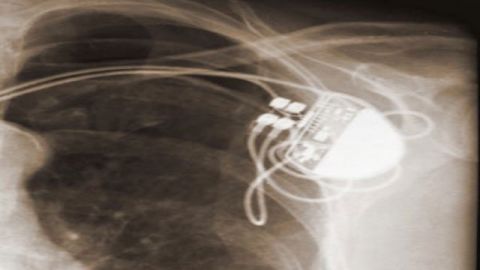

In the age of Moore’s Law and computer miniaturization, it should come as no surprise that these devices have shrunk significantly.  Now, for example, a heart’s pacemaker may be placed wholly in a self-contained apparatus resting entirely within the human chest.  There is no need for the constant connection to external devices, nor for the team of physicians to monitor the device at a patient’s bedside.  Now it is possible for a heart pacemaker to work on its own, based upon a set of pre-established operating instructions.

In the United States alone, hundreds of thousands of internal heart defibrillators have been implanted to regulate the damaged hearts of patients needing such assistance, including many well-know individuals, such as former US Vice President Dick Cheney. As a particularly polarizing public figure, it would not be surprising to learn that Mr. Cheney had a number of enemies and it was the job of the U.S. Secret Service to protect him from any threat–including any potential attacks against the critical technology implanted in his chest and upon which his life depended.

As medical devices have evolved and miniaturized, they have developed the capability of being controlled wirelessly, including remotely over the Internet. The benefits are obvious– wireless and remote control of implanted medical devices allow patients much greater mobility and obviate the need for daily trips to a doctor’s office.  In addition, these devices can dramatically lower health care costs, guaranteeing their wider user and acceptance moving forward.